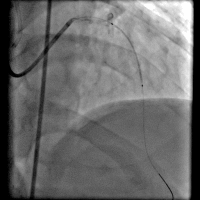

第一次手术过程

手术时间: 入院当天上午4点00分。

术中用药: 术中肝素3000单位。

手术过程(一): 将Runthrough NS 0.014″×180 cm导丝通过右冠病变放到右冠脉后降支远端,沿导丝送入抽吸导管反复抽吸。

手术过程(二): 沿导丝送入EXCEL 2.5×14 mm药物支架一枚至右冠中段,以14 atm×12 s释放。